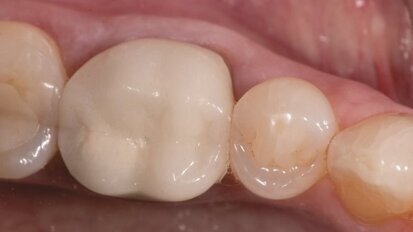

Znaczenie okluzji

Prawidłowa fizjologiczna odbudowa warunków zwarciowych stanowi duże wyzwanie dla każdego lekarza dentysty i technika dentystycznego. Nawet ...